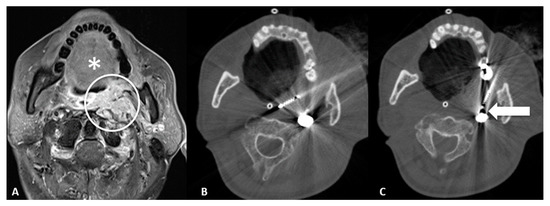

- Transglandular: This is a very useful approach in case of lesions in the pharyngeal space and prevertebral space, crossing the submandibular gland to reach these locations (Figure 3).

- Transflap: Useful in the case of early local tumor recurrence, in patients who underwent previous surgery, and myocutaneous flap reconstruction (Figure 4). The myocutaneous flap is usually devoid of significant vascularity and vital structures and presents a safe trajectory once it has been grafted [13].